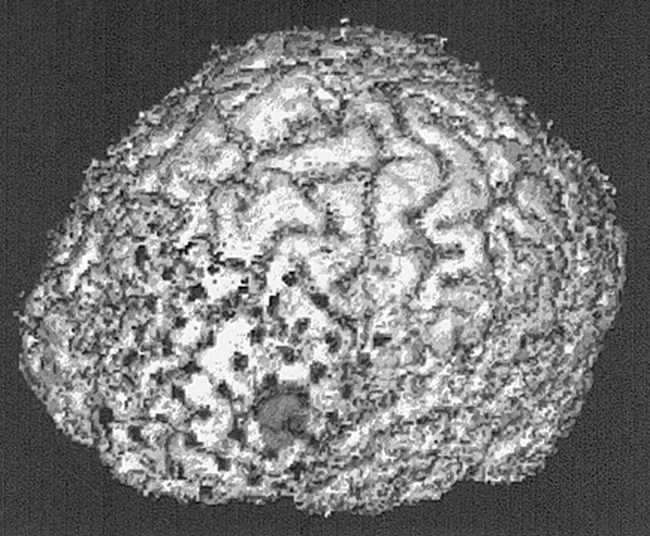

After intracranial electrode placement, patients underwent CT. Voxel dimensions were 0.590 × 0.590 × 3 mm. CT data were transported to an independent computer workstation. Using ANALYZE version 7.5 software, scans were converted to 8-bit images and reformatted to cubic voxel dimensions. Cubic voxel, 8-bit MR, and CT data were then converted to binary images, using thresholding to best emphasize the skin surface. Binary MR and CT studies were then surface matched using the binary MR as the base volume and the binary CT as the match volume. The surface matching coregistration algorithm was as described for the MR-SPECT coregistrations. Final matched CT voxel dimensions were 0.859 mm. For 3D visualization of intracranial electrodes, CT scans were thresholded to incorporate approximately only the upper 15% of gray-scale intensities. Figure 1A shows a volumetric CT scan segmented to depict the external surface. Figure 1B is the same scan reformatted by thresholding to include only the upper 15% of gray-scale intensities, which shows the 3D representation of subdural grid and strip electrodes.

A, CT scan shows segmentation to illustrate the external surface.

B, Same scan as A reformatted by thresholding to include only the upper 15% of gray-scale intensities to depict a representation of the subdural grid and strip electrodes.